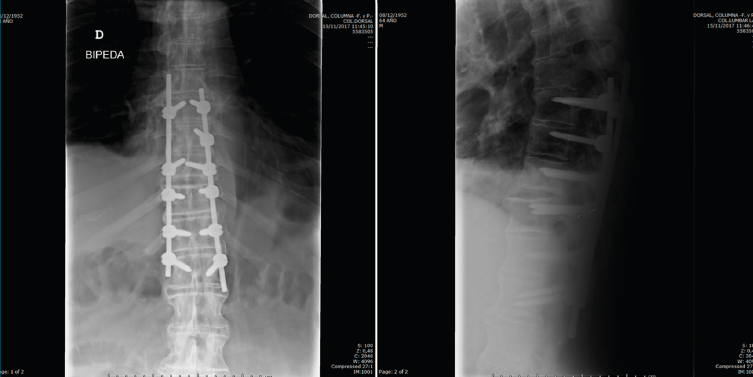

Figura 7. Control a los 2 meses de la cirugía.

Se realizó un control a los 2 meses de la cirugía, previo al inicio de rehabilitación (Figura 7).